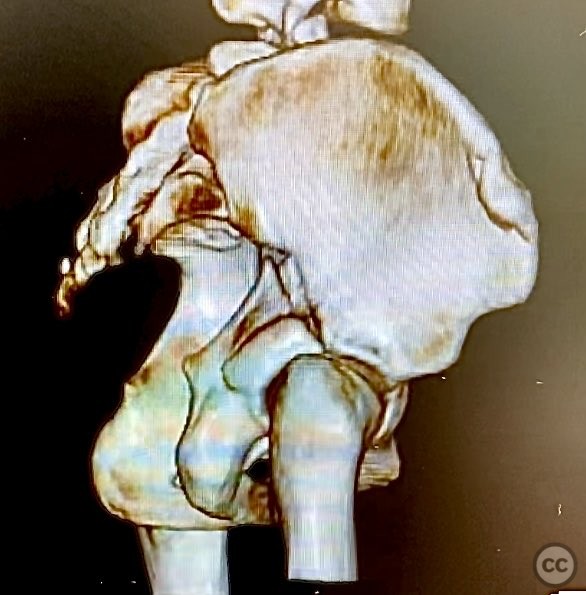

Clinical and radiological findings:  The patient is morbidly obese and sustained an unstable, displaced posterior column/posterior wall (PC/PW) acetabular fracture. Axial computed tomography images revealed a 2x2x1.5 cm pyramidal chondrocancellous articular fragment wedged in the fracture plane near the incisura ischiadica major (greater sciatic notch). Surface-rendered reconstructions further delineated the fracture morphology and fragment position. Obesity was noted to complicate all aspects of management, including anatomical localization, intraoperative imaging, and soft tissue handling.

Morbid obesity significantly complicated intraoperative exposure, anatomical landmark identification, retraction, and fluoroscopic imaging. A 2mm pin placed under C-arm guidance facilitated accurate identification of the femoral shaft for limb positioning. Retrieval of the intra-articular chondrocancellous fragment required careful dissection near the greater sciatic notch. After reduction of all fragments, contoured plates and screws were applied to maintain stability. Postoperative imaging confirmed accurate reduction and appropriate implant placement. Wound management strategies were employed to mitigate increased risk of complications associated with obesity.